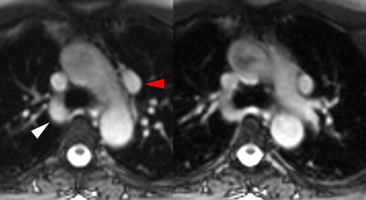

Veine cave supérieure double. La veine cave supérieur droite est en place avec drainage normal de la crosse azygos (flèche blanche). La confluence veineuse brachio-céphalique gauche se continue par une veine cave supérieure gauche qui longe le bord gauche du cœur contre le sillon mitral et se draine dans le sinus coronaire.